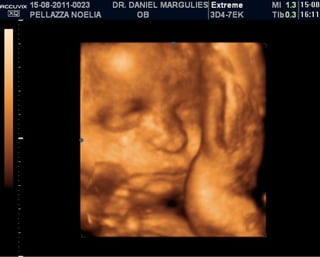

ISABELLA!

ISABELLA! Está viniendo!